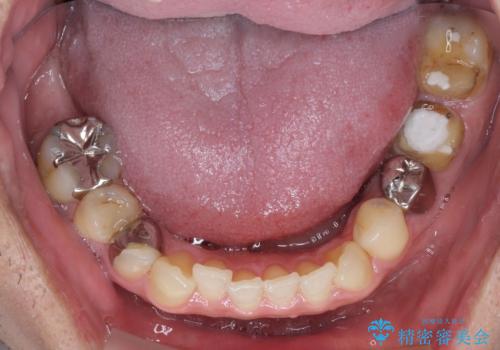

目立つ銀歯と欠けてしまった詰め物 オールセラミッククラウンでの補綴治療